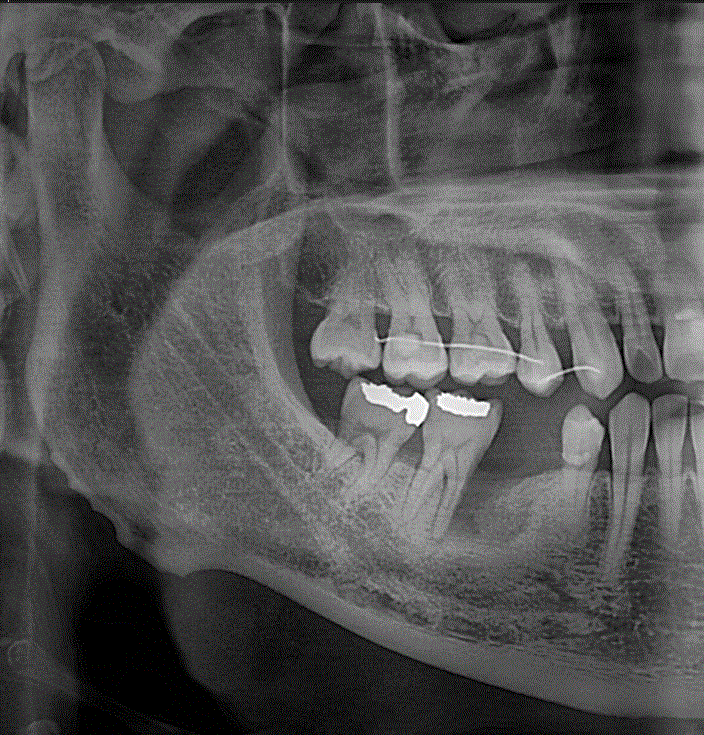

상악동 거상술을 이용한 임플란트 수술하기

안녕하세요. 최근에 왼쪽 위에 어금니가 없는 환자가 한 분 오셨습니다. 뼈가 많이 부족해 뼈이식을 동반한...